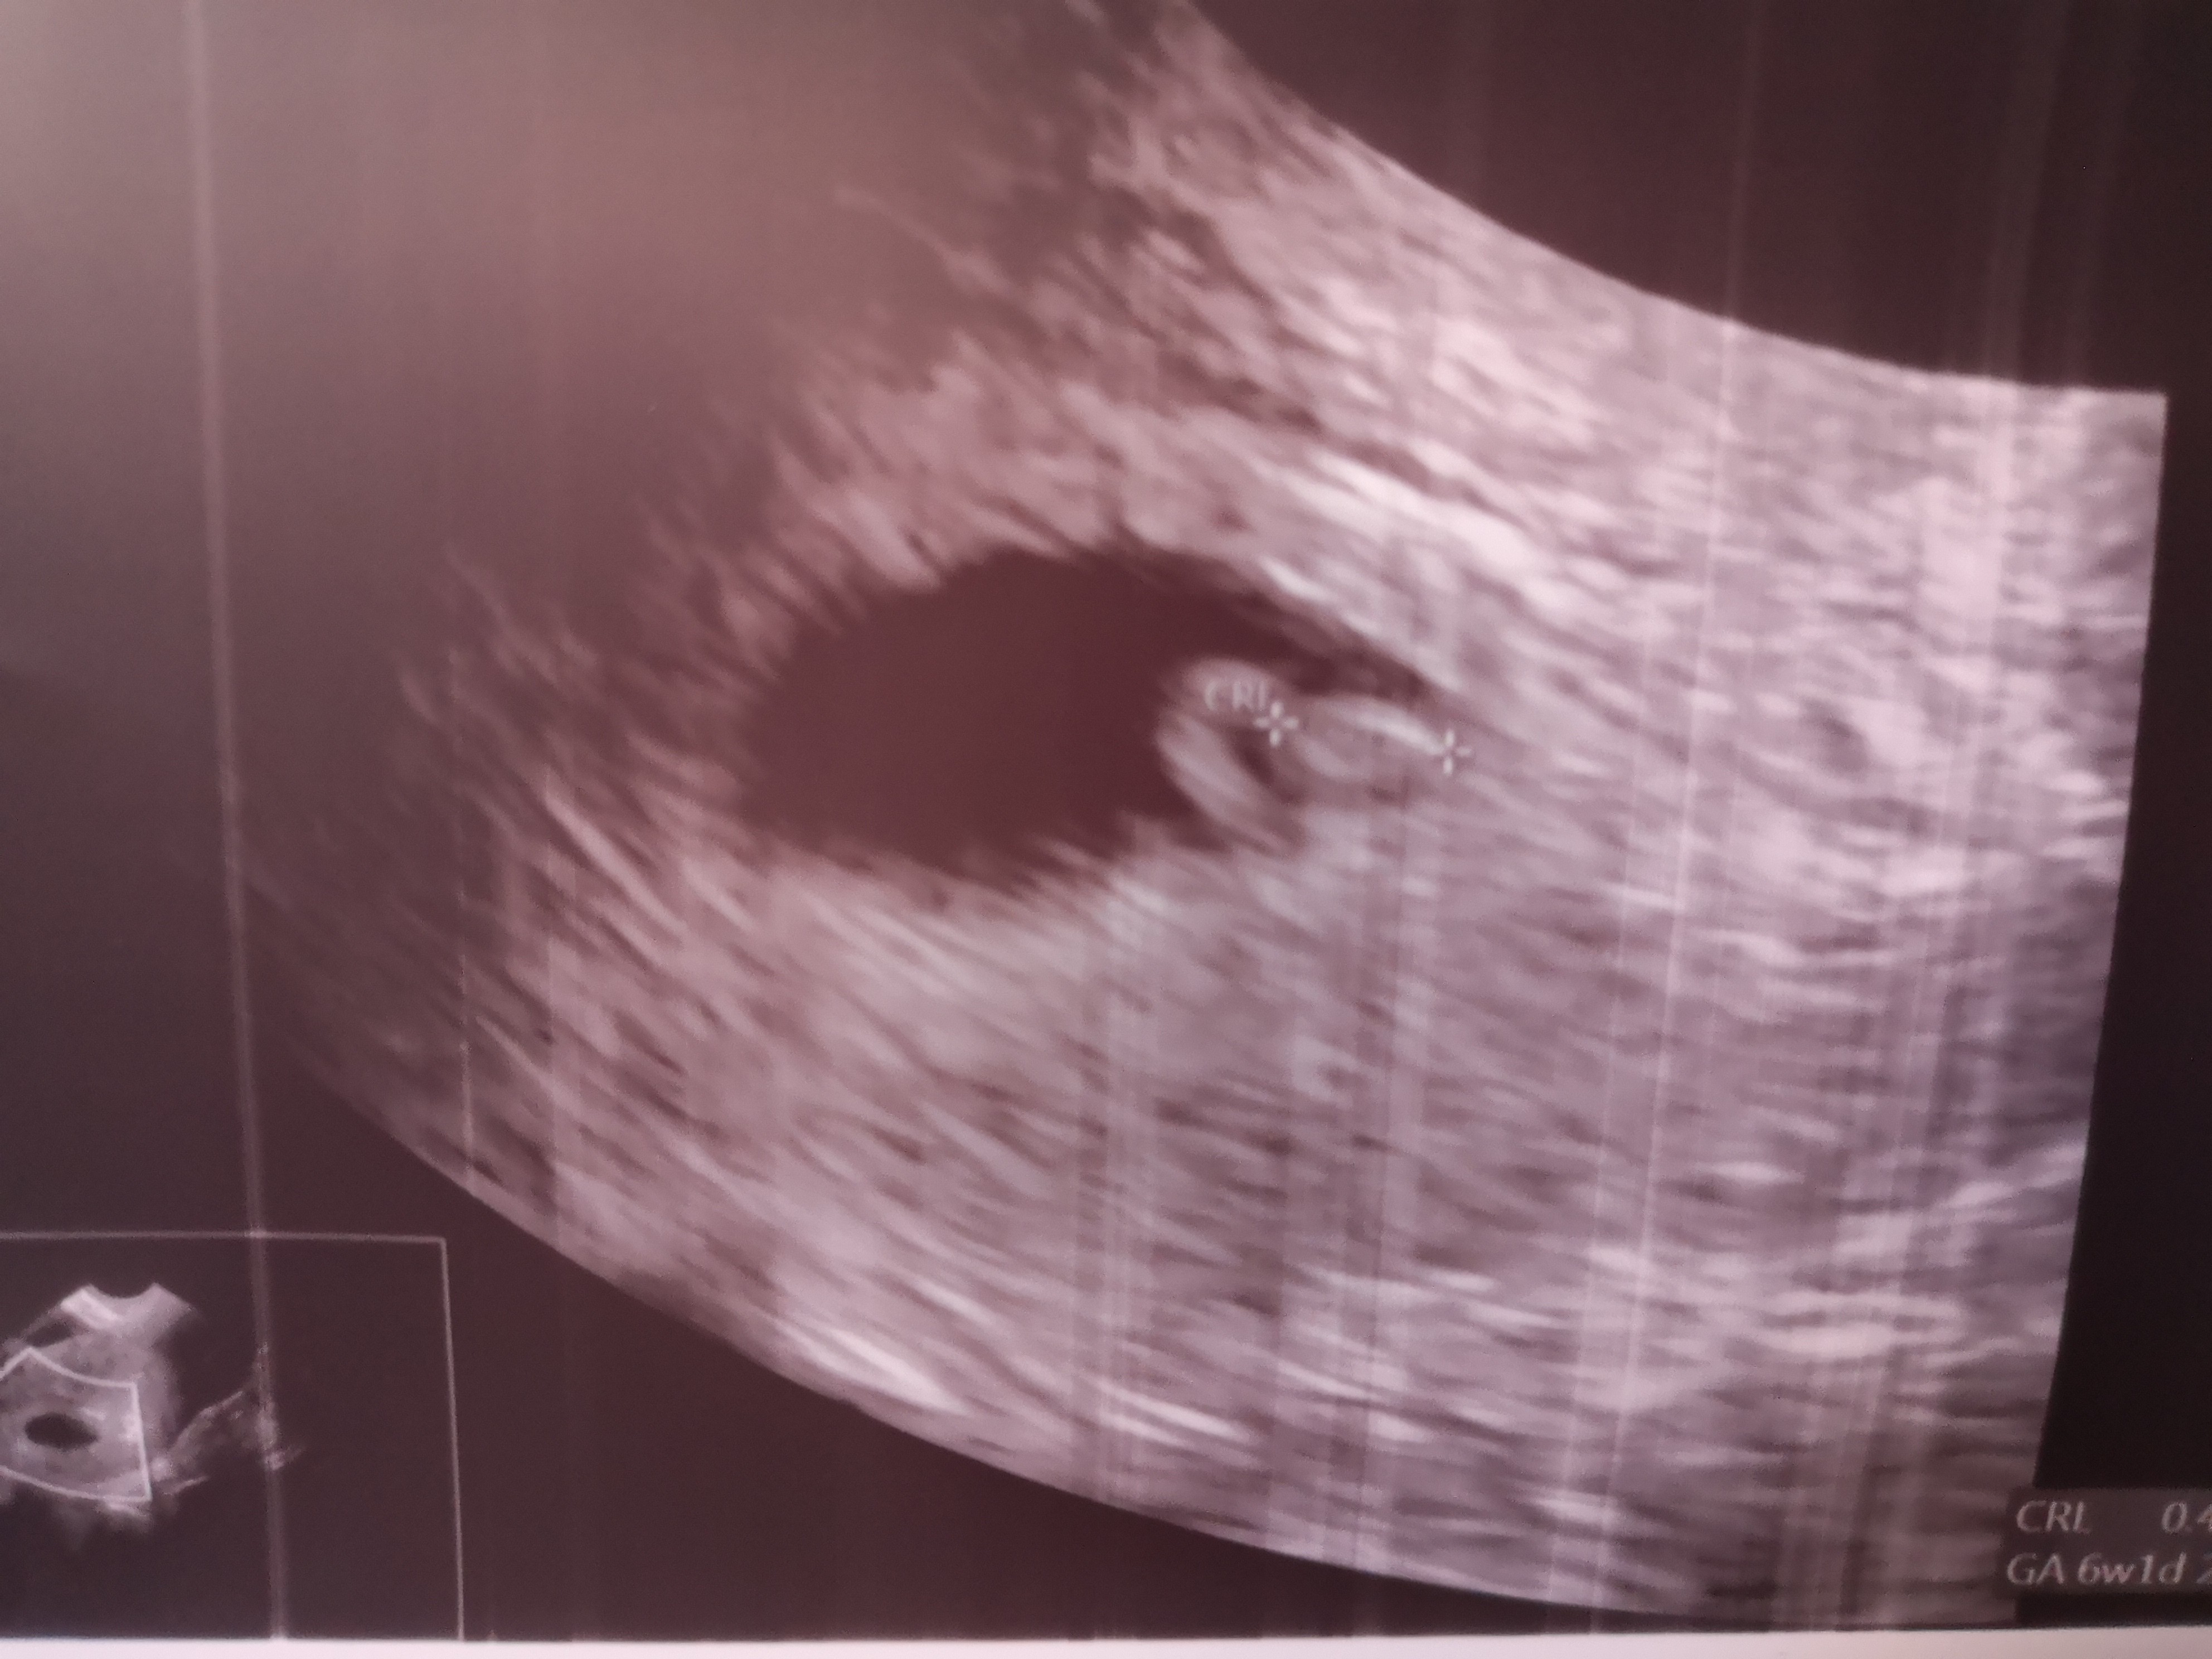

Wystarczy, że owu przesunęła się 2-3 dni i już na serduszko za wcześnie.